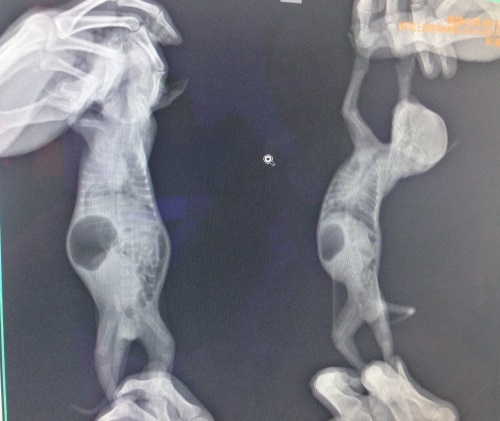

主題: 小貓肺炎死亡母貓漲奶嚴重 申請者姓名: 臺北市支持流浪貓絕育計劃協會 花色: 申請日期: 2014-05-30 14:31:48 申請者部落格: 申請者臉書網址: 所在縣市/合作醫院: 台北市/欣旺動物醫院 治療費用: 3500元 需求人數: 8人 已結案 (2014-07-02 17:28:31) 報名人員: 帕尼尼(已付款)、Tina Wu(已付款)、Carlos Kang x6(已付款)、 候補人員: 動物病情說明: 蚌麵貓媽媽在安養之家哺育五個孩子,每隻都肥滋滋,某天其中一隻小貓被貓貓孤立,照顧員把小貓放到貓媽媽身邊,過一會小貓又單獨在外面,把小貓抓起來查看,肚子還是鼓鼓的,沒有異樣,隔天小貓往生,百思不得其解,將其中比較瘦小的貓送至醫院檢查,拍攝X光發現小貓肺部都有感染的狀況,只有一百多公克,無法使用藥物,只能給予噴霧用葯,當天晚上小貓陸陸續續離開,雖然外面天氣變化大但室內的溫度平穩,哺乳環境安靜舒適,小貓還是有感染的問題,很難想像外面餵奶的貓媽媽和小奶貓要怎麼度過,小貓離開之後,貓媽媽不肯吃東西,擔心是脹奶引起不適,緊急送到醫院裝置洗衣袋內檢查,發現整個胸口硬梆梆,一量體溫40.5度,趕快給予抗生素幫助退奶,打水份降溫,住院治療觀察兩周後已由志工R回。